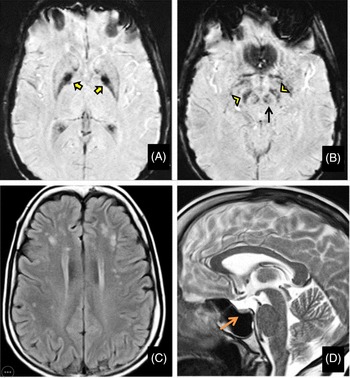

Her routine blood investigations were normal except for hyperglycemia. Electrocardiogram and echocardiography were within normal limits. Pure tone audiometry showed bilateral mild sensorineural hearing loss. Magnetic resonance imaging (MRI) brain showed mineralization in bilateral globus pallidus interna, substantia nigra, and red nucleus on susceptibility-weighted images (SWI) (Figure 1A and B) along with bilateral frontoparietal discrete white matter hyperintensities on T2-weighted images(Figure 1C) and partial empty sella with small-sized hypophysis (Figure 1D). Serum estradiol level of 23.2 pg/mL (normal range in premenopausal females being 30–400 pg/mL) and progesterone levels of 0.04 ng/mL (normal range being 0.1–0.7 ng/mL in the follicular stage and 2–25 ng/mL in the luteal stage) were low, whereas serum follicular stimulating hormone (FSH) level of 33 IU/L(normal range 3–10 ), luteinizing hormone (LH) level of 27.4 IU/L (normal range 2–8 ) were high suggesting a hypergonadotropic hypogonadism secondary to ovarian failure. Ultrasound pelvis showed a small infantile uterus with ill-defined ovaries.

Figure 1: Magnetic resonance imaging (MRI) of the brain shows mineralization in bilateral globus pallidus interna (yellow arrows), substantia nigra (yellow arrowheads), and red nucleus (black arrow) on susceptibility-weighted images (A and B) along with bilateral frontoparietal white matter hyperintensities on T2-weighted images (C) and partial empty sella with small sized hypophysis (D-orange arrow).